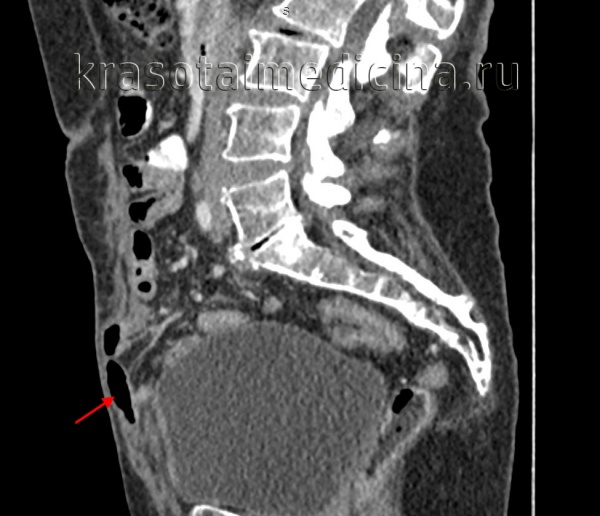

КТ ОБП/ЗП. Дефект передней брюшной стенки с пролабированием петли кишки (красная стрелка) в подкожную клетчатку.